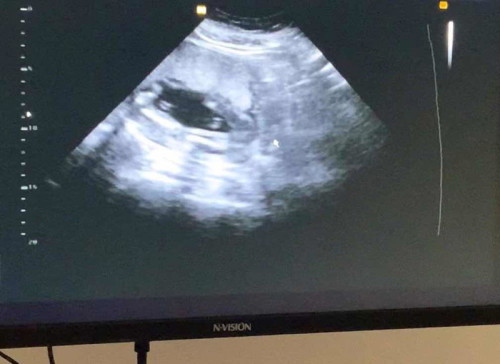

I’m 19 weeks pregnant, nagpaultrasound po ako to know the the gender po ni baby ko. Ano po sapalagay nyo gender nya?

Pelvic ults